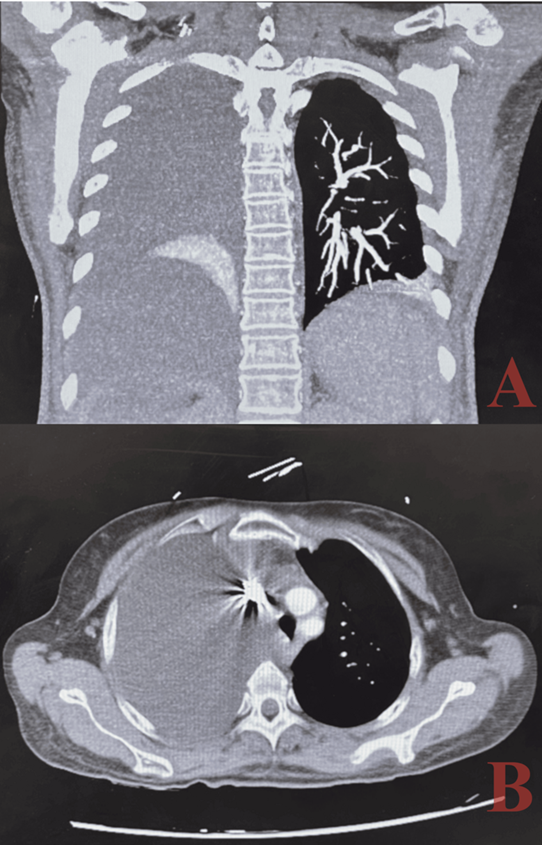

Imaging studies:

chest radiography and computed tomography (ct) scans are pivotal in identifying

pleural effusions and assessing the extent of lung involvement. In this case,

imaging revealed a significant right-sided pleural effusion with near-total

lung collapse and mediastinal shift, underscoring the severity of the

presentation. Ct angiography additionally confirmed liver morphology consistent

with cirrhosis and excluded pulmonary embolism.